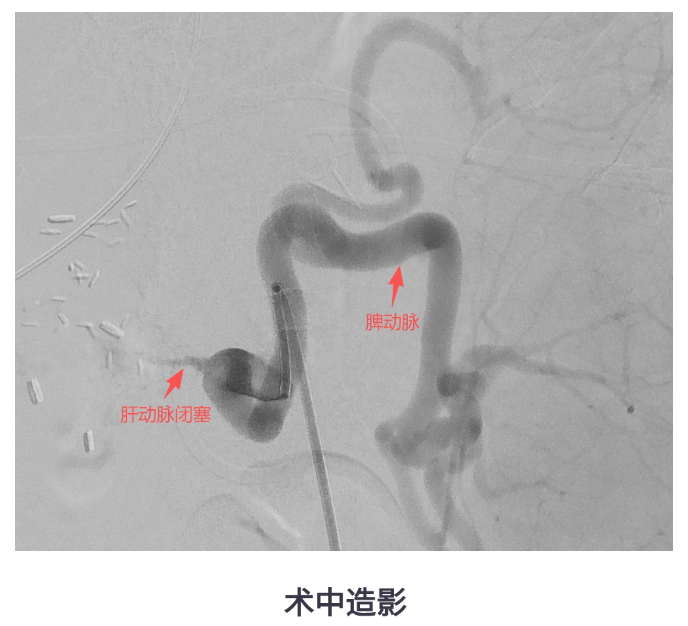

转入我院后,CT显示患者肝脏包膜下积气、肝右叶低密度影,提示脓肿复发,同时存在门静脉高压、脾大、肝动脉狭窄等复杂情况。医疗团队决定为她实施经导管脾动脉栓塞术(SAE),并同期进行肝动脉造影和压力测量。

术后,王女士的门静脉压力从术前的较高水平明显下降,肝动脉血流改善,发热控制,病情稳步好转。SAE不仅缓解了脾功能亢进,还间接改善了患者的肝动脉供血,为控制脓肿创造了有利条件。